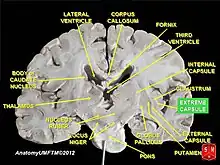

La capsule extrême (en latin : capsula extrema) est un ensemble de tractus de fibres blanches (formées d'axones) situées entre le claustrum (appelé également l'avant-mur) et le cortex insulaire[1]. Cette capsule extrême est aussi décrite comme une fine capsule de substance blanche en tant que fibres d'association (en) corticocorticales (c'est-à-dire que ces fibres sont responsables de relier le cortex cérébral avec une autre aire corticale)[2]. La capsule extrême est séparée de la capsule externe par le claustrum, et la capsule extrême sépare le claustrum du cortex insulaire, et tous ces éléments se trouvent latéraux par rapport aux composants du corps strié[2],[3].

Allant de la ligne médiane du cerveau vers le côté, la capsule extrême est la plus externe par rapport à la capsule externe et à la capsule interne[4].

Elle est plus facilement visible dans une coupe horizontale (transversale), juste latéralement au claustrum.